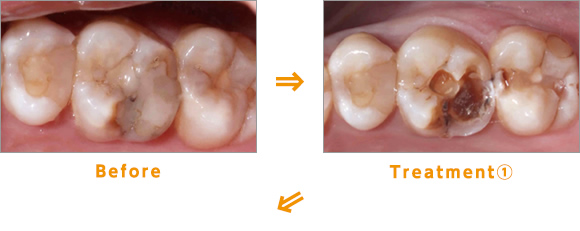

虫歯治療

虫歯治療で感染した象牙質を除去した部位には、コンポジットレジン修復、インレー修復、クラウン修復にて失った歯牙を回復します。保険治療で使用する金属は金銀パラジウム合金を使用します。見た目は良くないですが、機能改善には全く問題ありません。

Before:歯の咬合面と隣接面に虫歯ができている症例です。

Treatment1:最小限侵襲治療の考え方で虫歯を慎重に除去していきます。

Treatment2:感染象牙質を除去できたら型取りをします。

After:保険の金銀パラジウム合金のインレーを装着します。